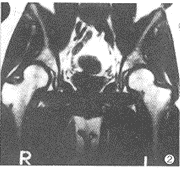

正常对照组: 腰椎T1WI表现分为两组,<20岁25例,均为椎体中间部出现条带状高信号,其余为均匀稍高信号;>20岁10例,表示为椎体内不均匀斑片状高信号。髂骨35例中,T1WI表现为稍高信号背景中仅在髋臼中上部见不规则斑片状高信号灶或并有髂骨不规则小斑片状高信号灶。股骨近段T1WI表现:>20岁的10例均表现为较均匀高信号;10~20岁的14例表现为稍高信号背景下可见斑点、斑片状高信号相互交错分布;<10岁的11例均表现为较均匀的稍低信号。腰椎、骨盆及股骨上段T2WI表现均为均匀的等信号(图1、2)。

图1 男,24岁。正常腰椎。A.T1WI腰椎椎体呈稍高均匀信号。B.T2WI椎体呈等信号 图2 正常骨盆,T1WI髂骨、股骨上段均呈均匀高信号